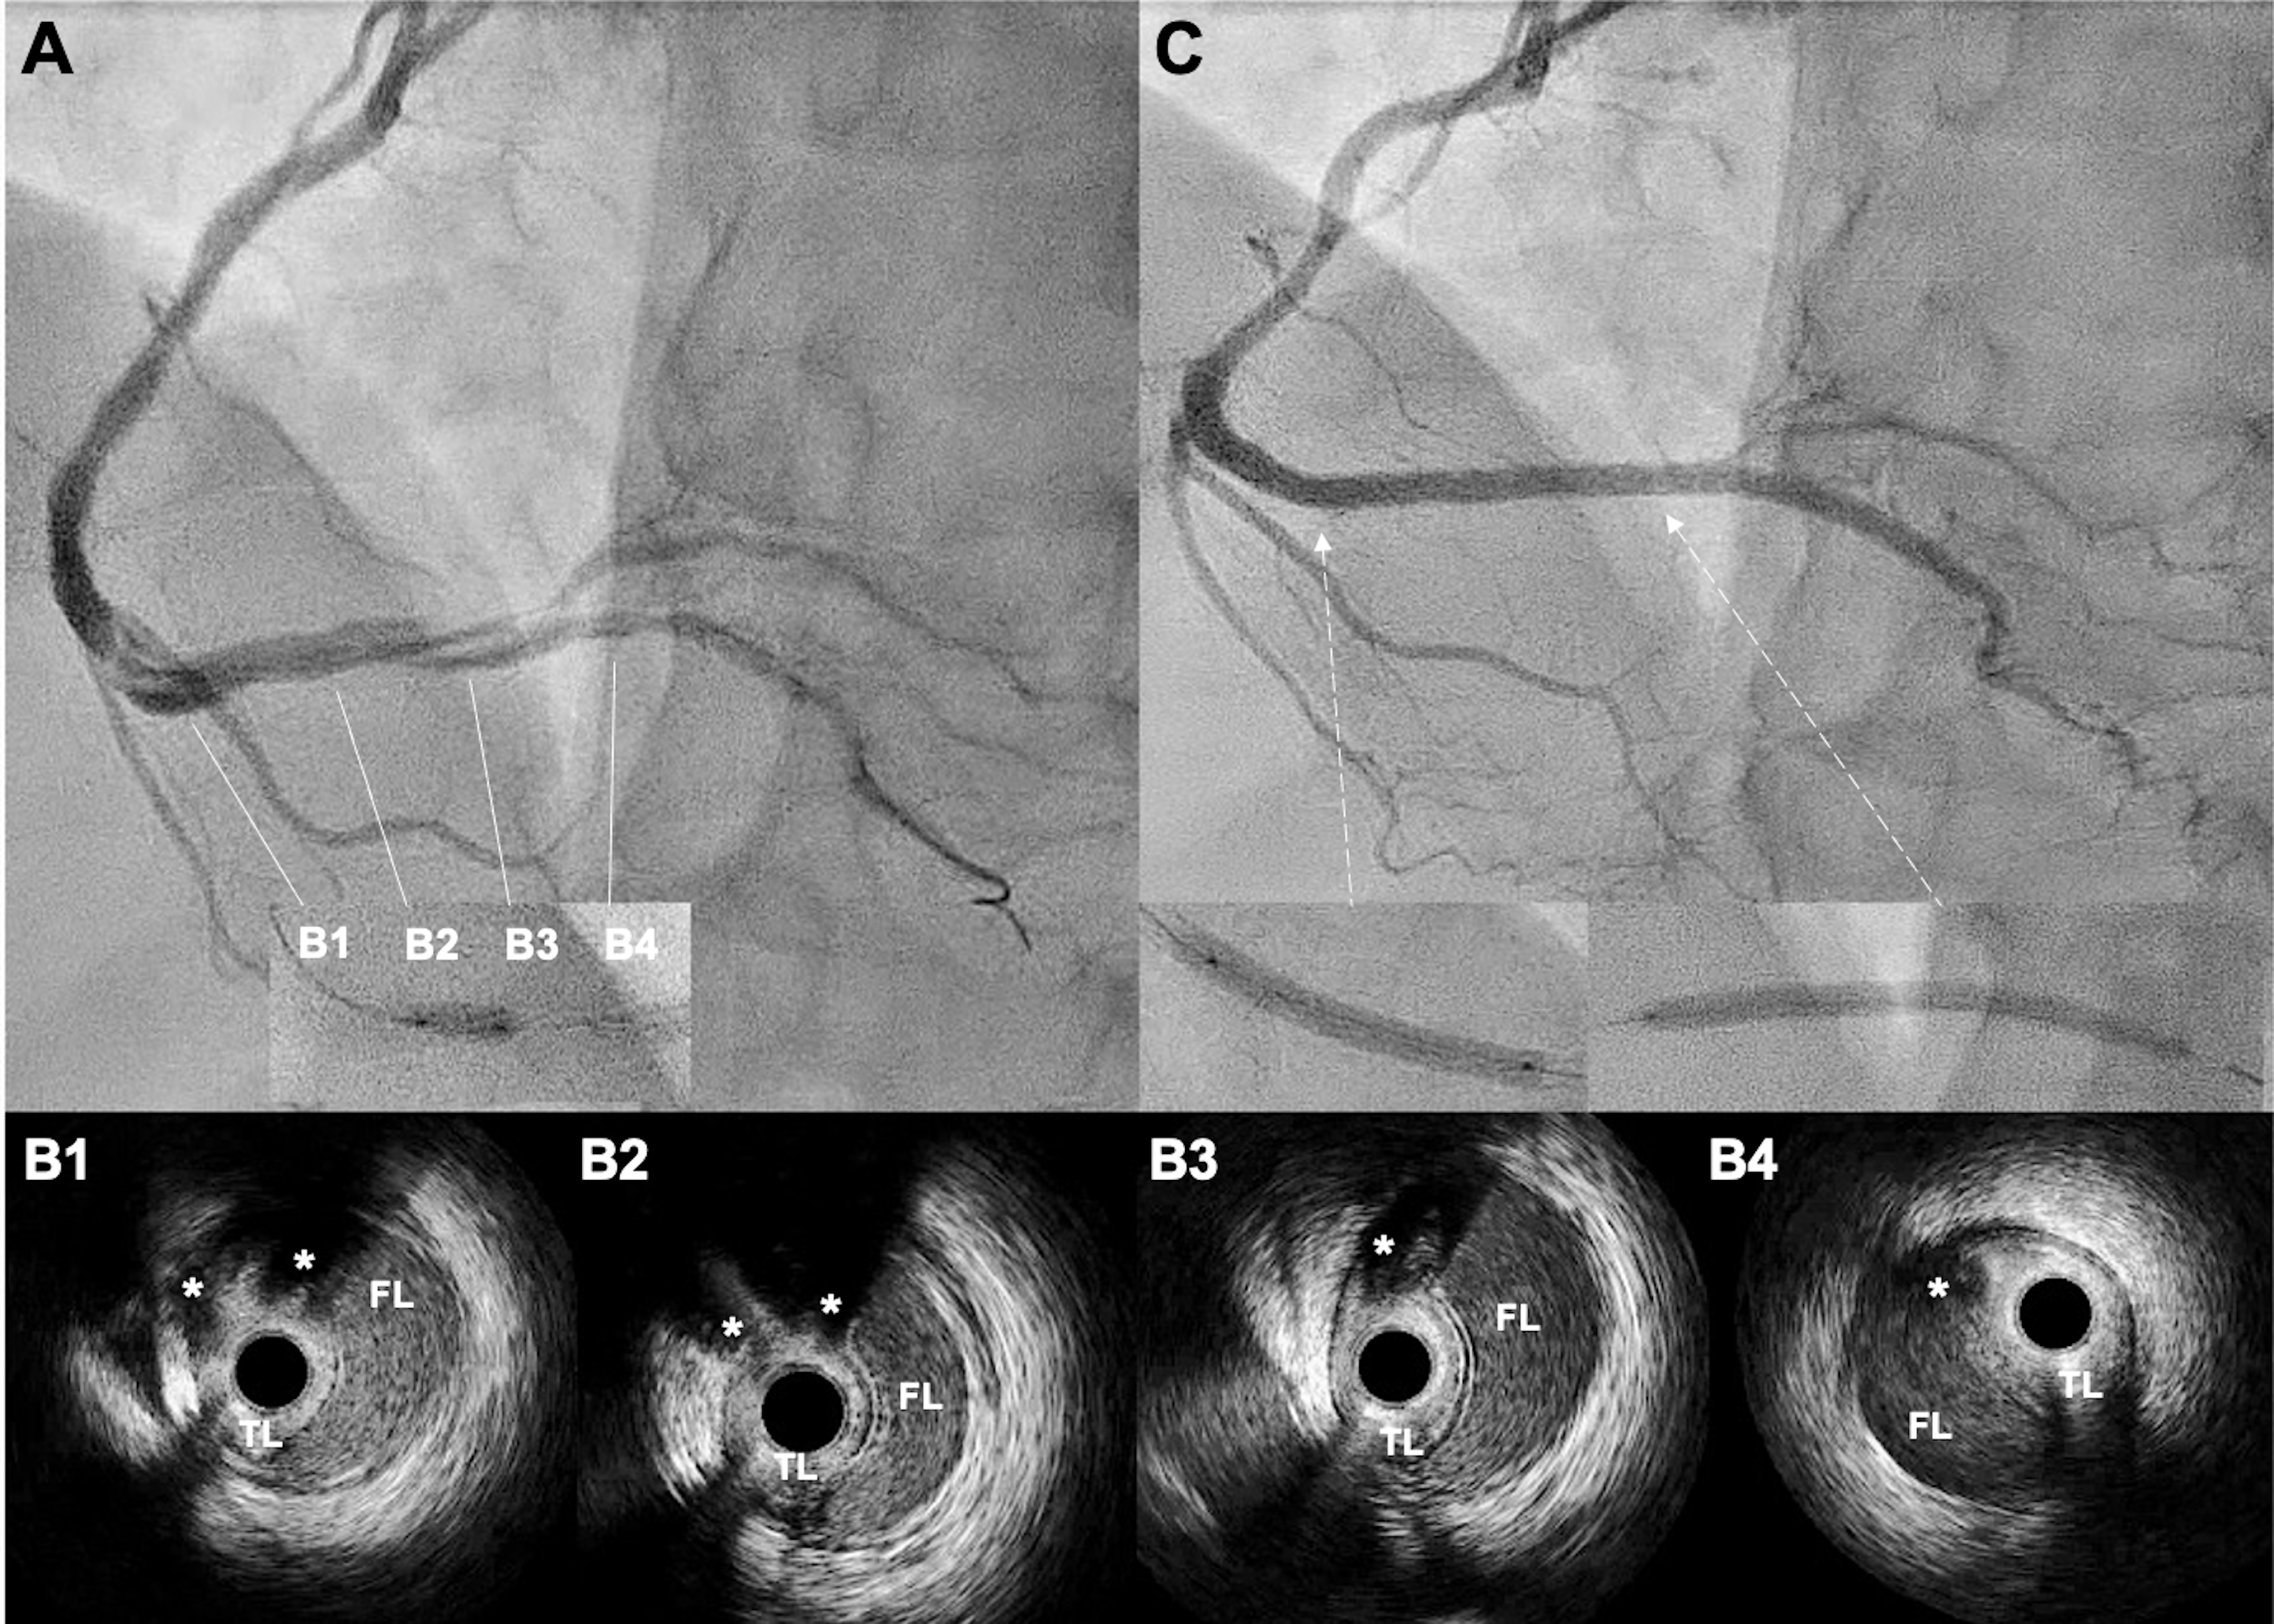

A 42-year-old man was admitted with an inferior ST-segment elevation myocardial infarction. Emergency coronary angiography (CAG) revealed a critical lesion of the middle right coronary artery (RCA) (Figure 1A), which was treated with a 3.5 x 18-mm zotarolimus-eluting stent (ZES) (Figure 1B, Video 1).